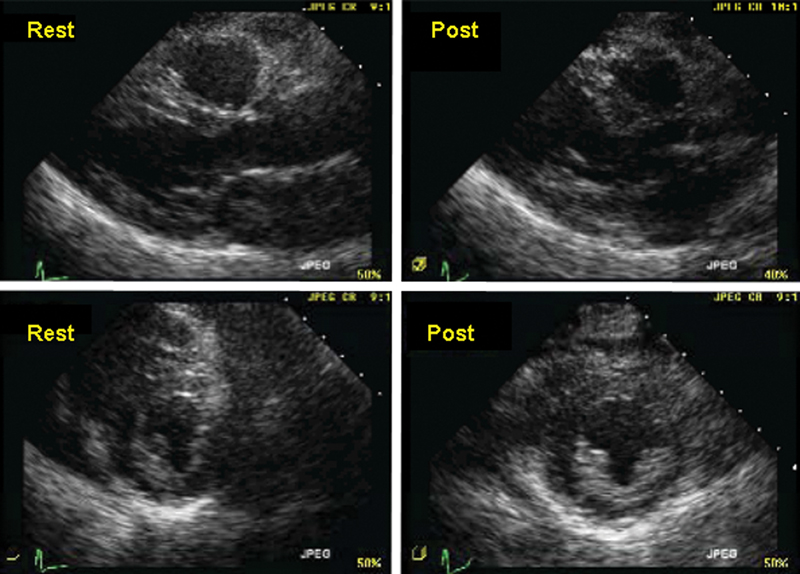

فحوصات تشخيصية لبعض امراض القلب والشرايين التاجية